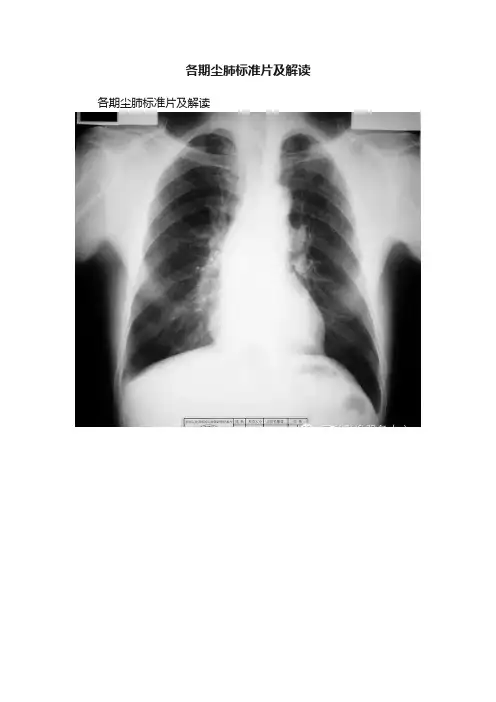

各期尘肺标准片及解读各期尘肺标准片及解读